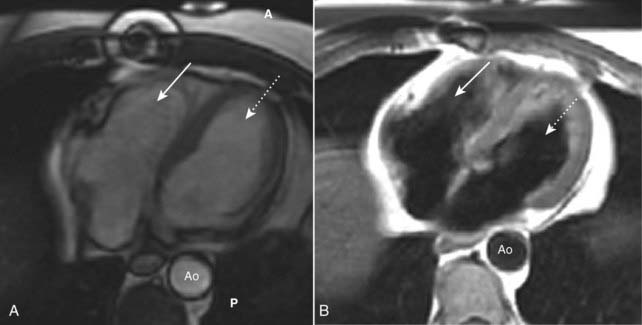

image

Figure 9-2 Pericardial effusions, small and large.

A, Fluid first begins to accumulate in the dependent portions of the pericardial space which is posterior to the left ventricle in the supine position (solid white arrow). B, As the effusion increases in size, it fills the pericardial space and encircles the heart (dotted white arrows). Conventional chest radiographs may show an enlarged cardiac silhouette but cannot differentiate the density of the heart from the effusion.